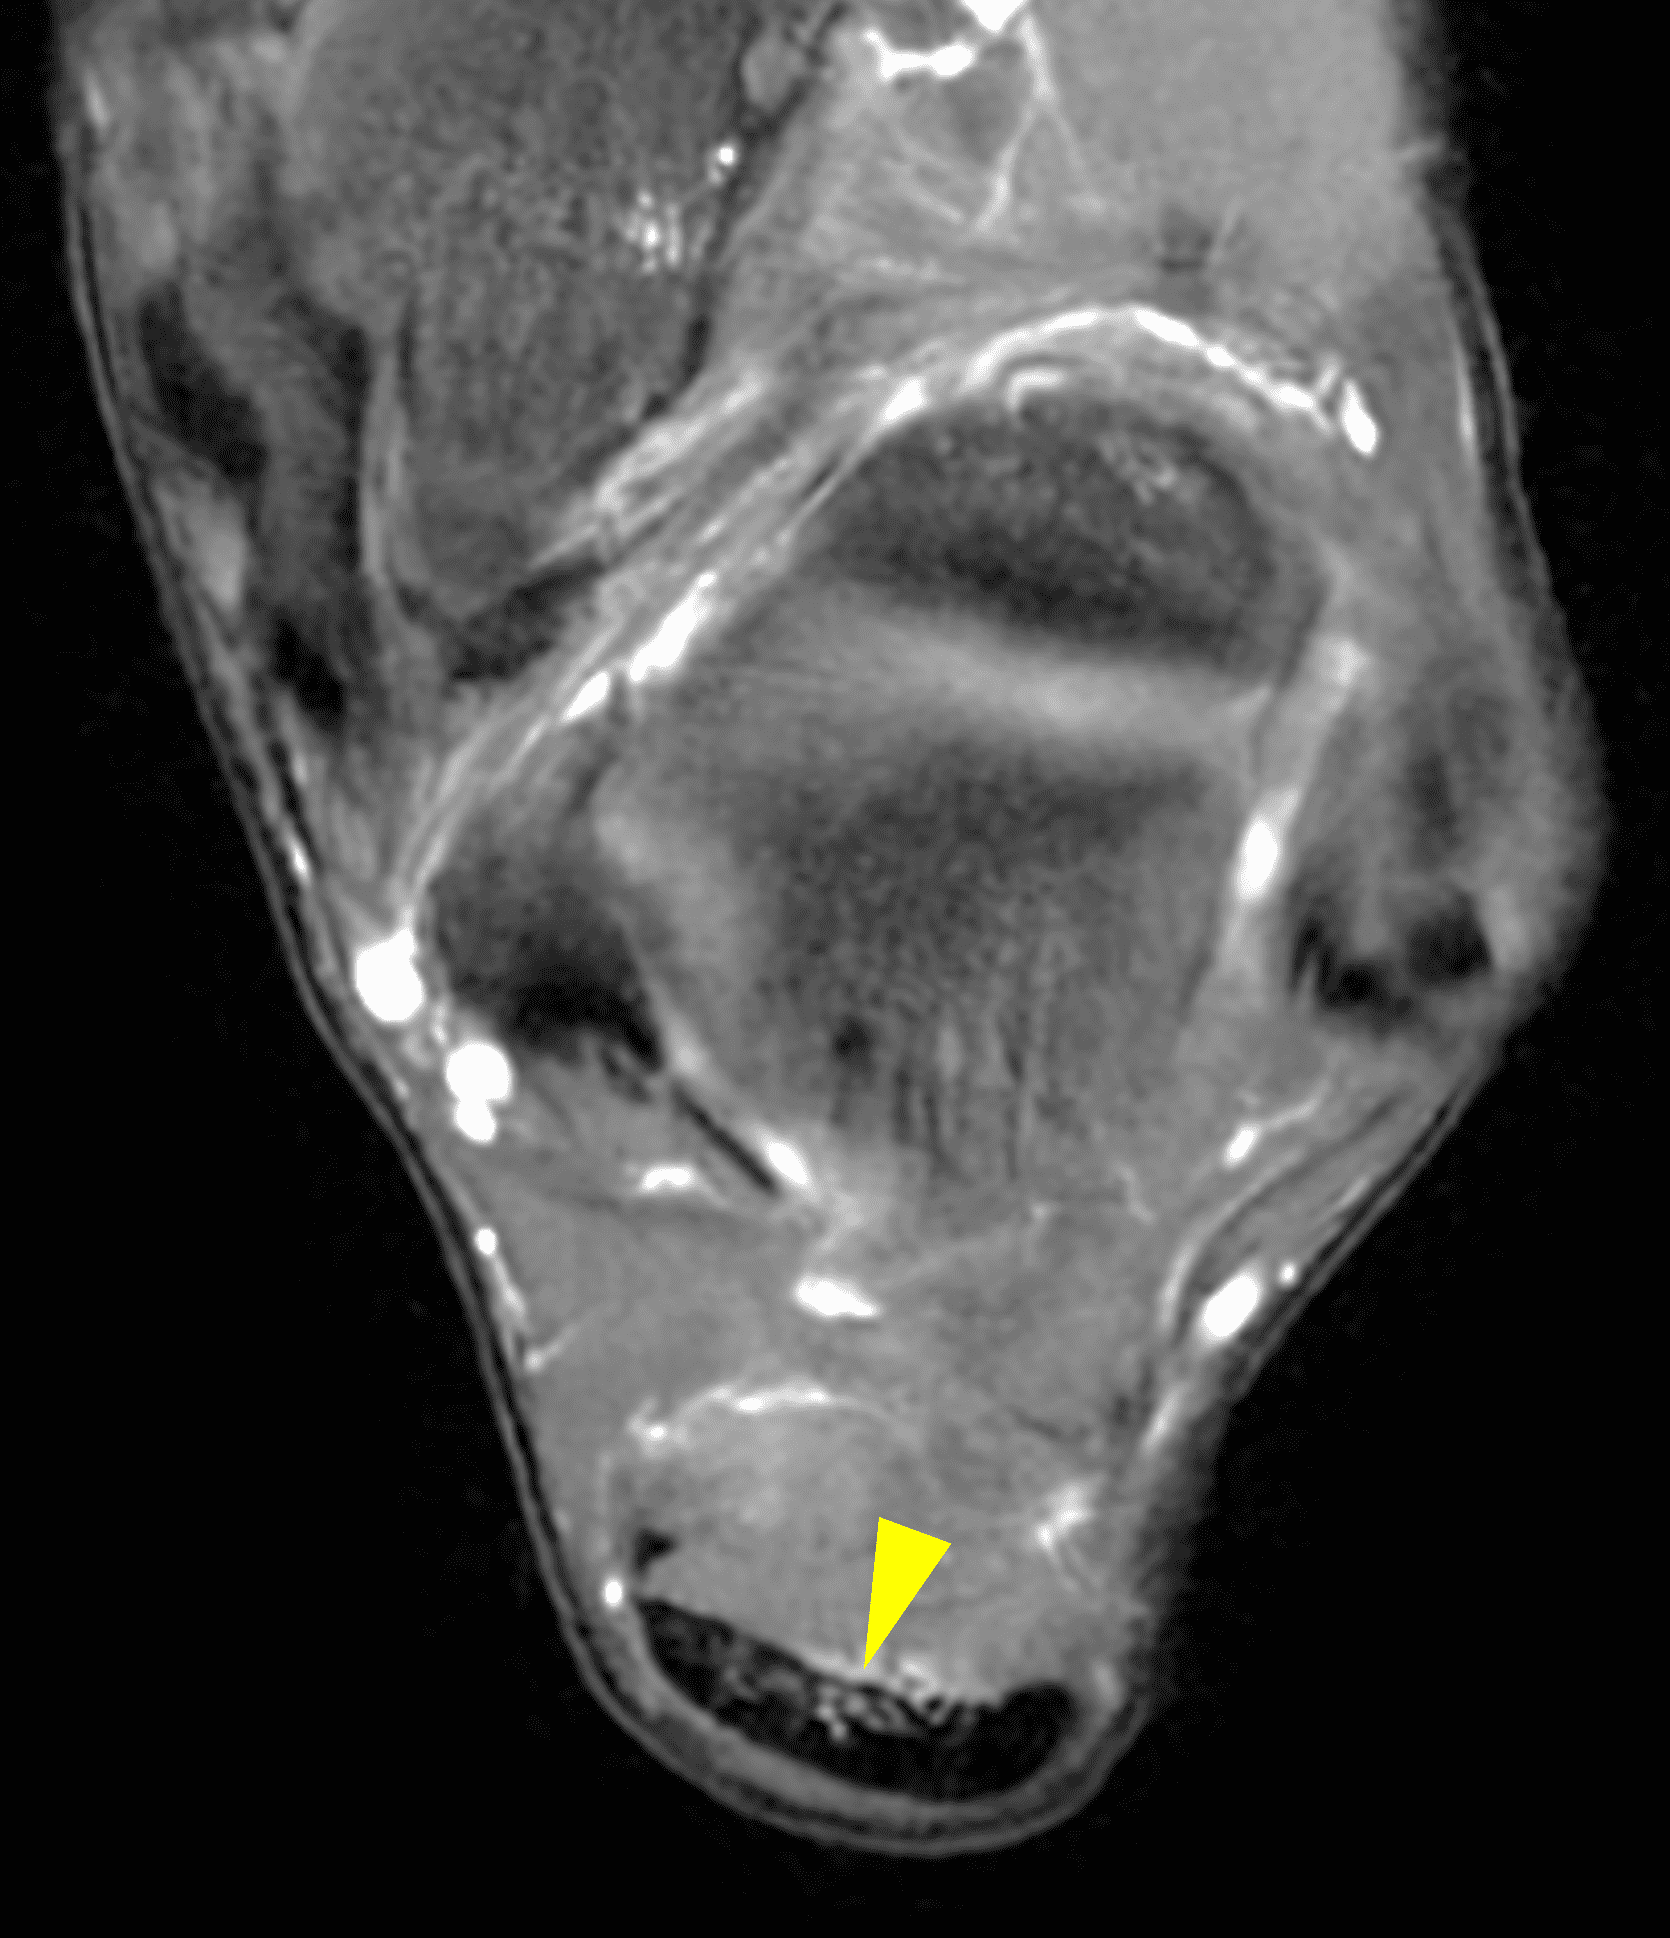

Figure 2: Complete Achilles tendon rupture. (2A) The lateral radiograph shows a thick and indistinct proximal Achilles tendon contour (arrows). (2B) A fat-suppressed T2-weighted image shows complete rupture of the tendon with a fluid-filled gap (yellow arrow) measuring 1.5 cm in length, located 10 cm cranial to the tendon insertion (blue arrow) and just distal to the edematous myotendinous junction (red arrow). The tear is superimposed on diffuse tendinosis. (2C) A sagittal T1-weighted image confirms the diffuse tendinosis. Fluid extends anteriorly into Kager’s fat pad (arrow) suggesting disruption of the anterior paratenon. (2D) A transverse fat-suppressed T2-weighted image through the proximal tendon shows no intact fibers (arrow), confirming the full-thickness rupture.